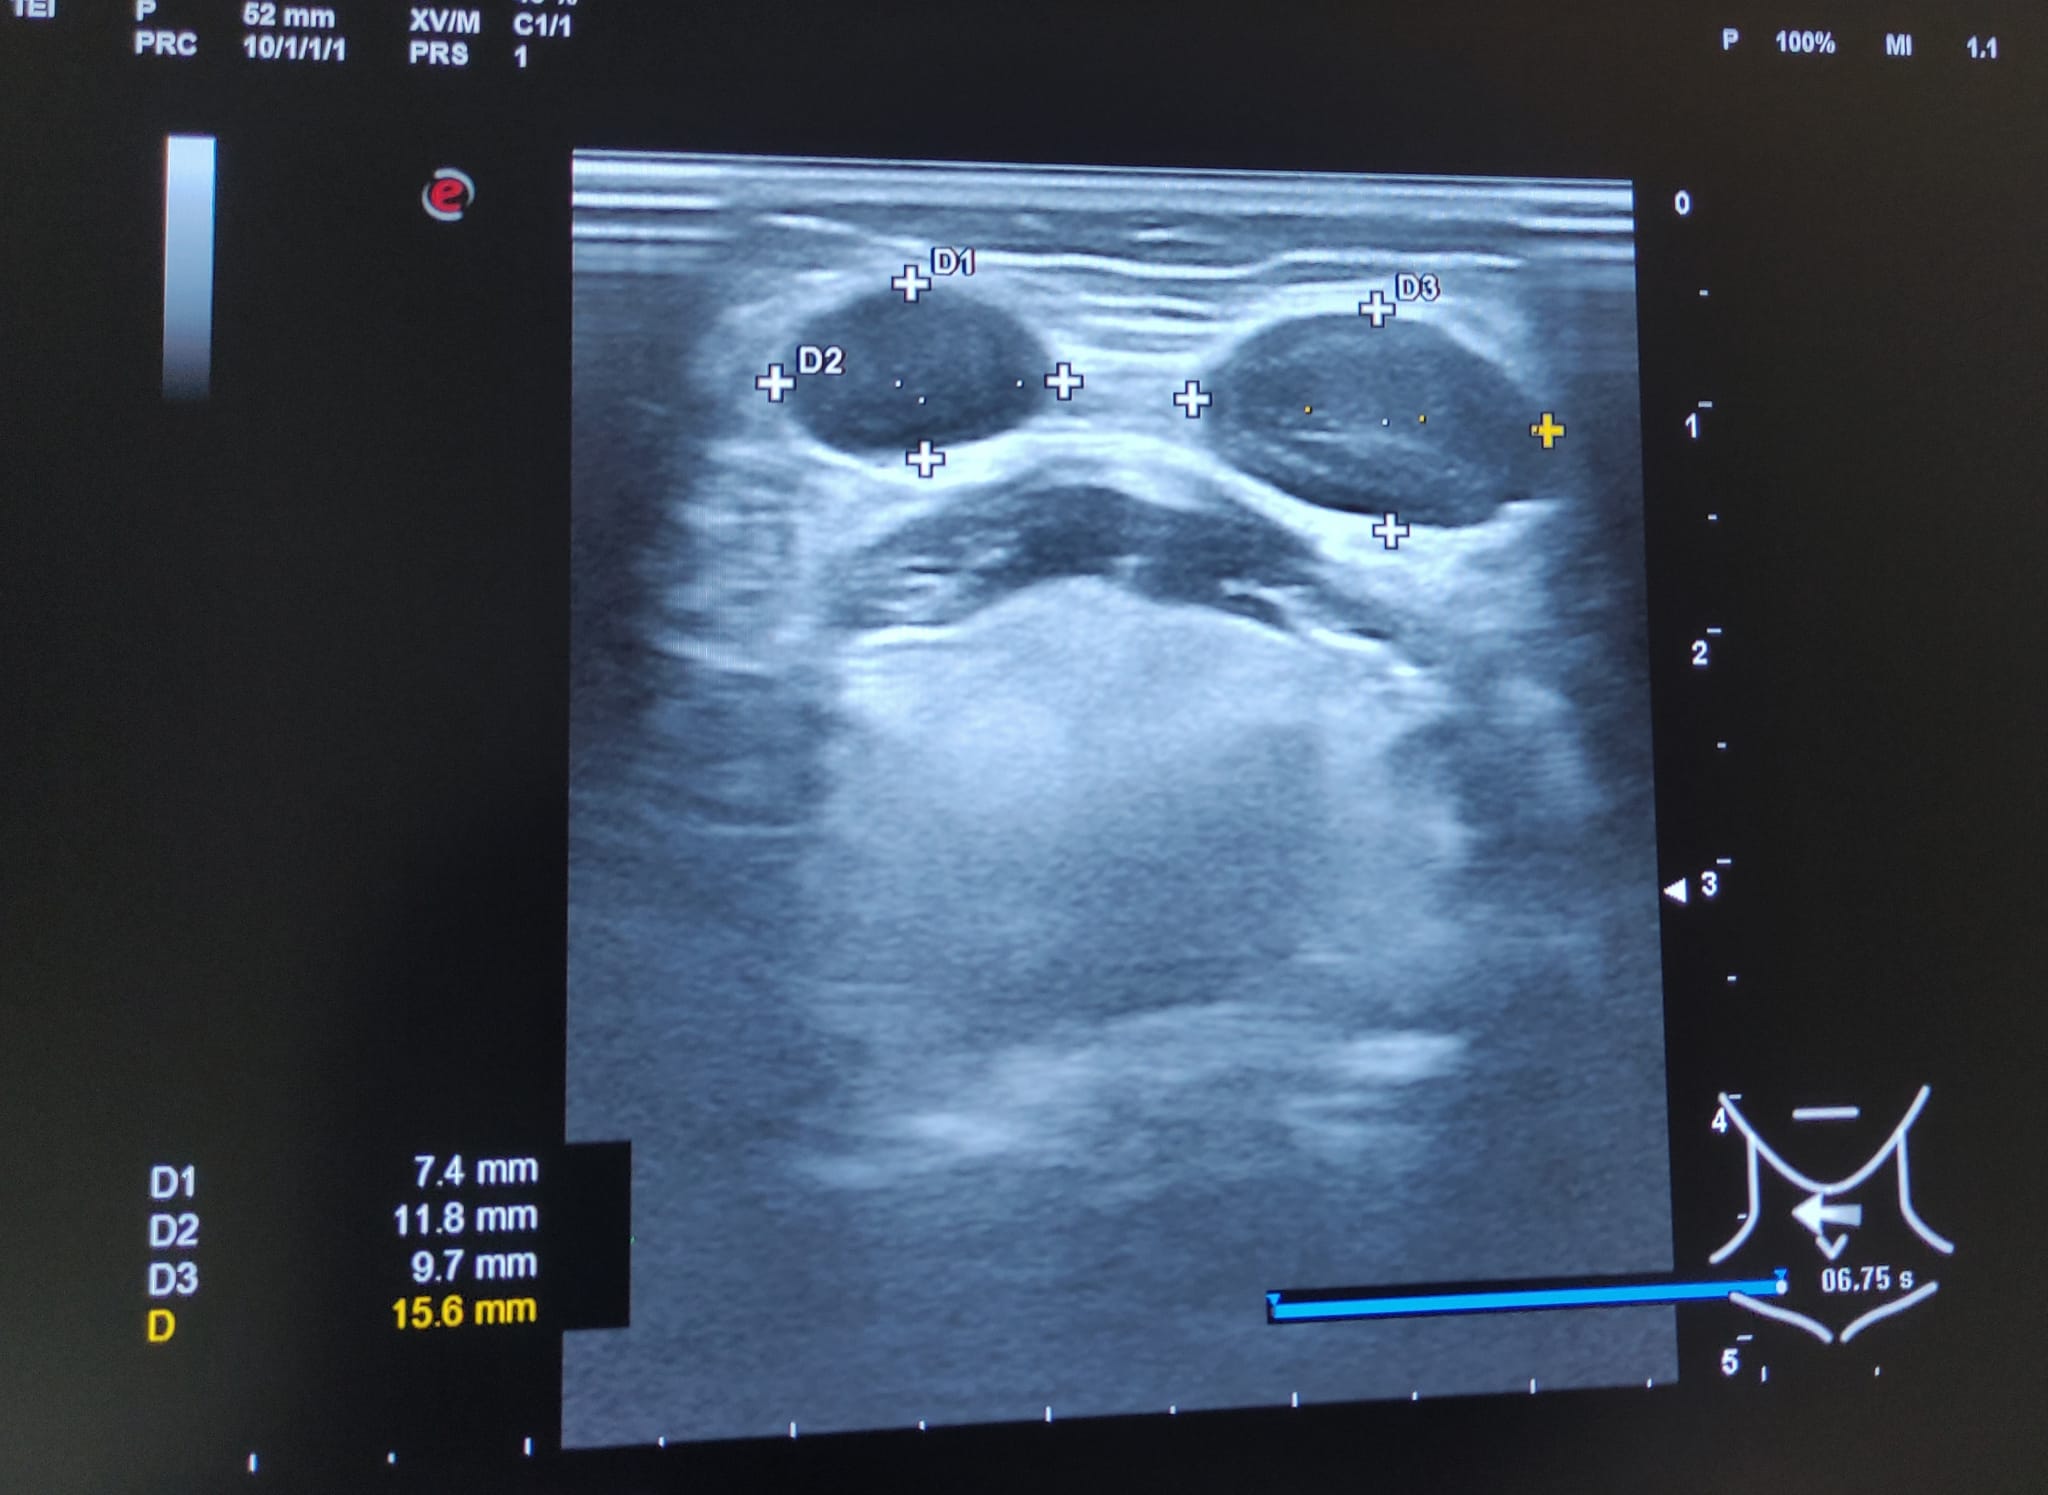

Hallazgos ecográficos

Múltiples adenopatías (más de 12) de varios tamaños siendo la mayor de 2 cm y de morfología redondeada, alguna sin hilio ni centro graso.

A los 3 meses se realiza nueva ecografía sin observar cambios significativos en las adenopatías ya visualizadas. Paciente permanece asintomática.